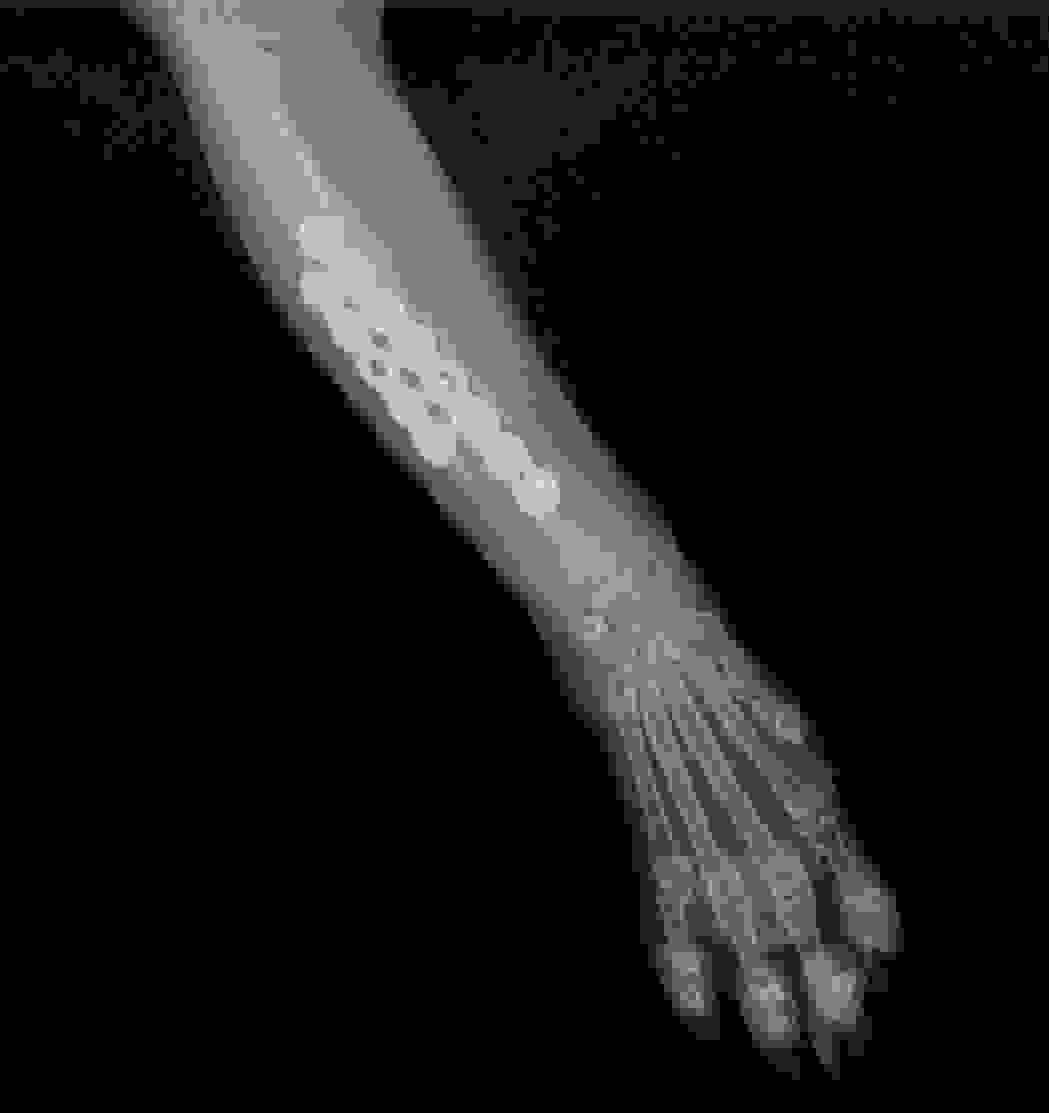

VEC的骨科服務建基於先進的醫療技術與緊密的團隊合作。中心採用國際認可的SecurosTM骨科用品,提供高品質的骨板、骨釘及外固定選項,以應對各類骨折修復與關節穩定手術。手術前,獸醫團隊會利用電腦斷層掃描獲取詳盡的立體影像,為制定精準的手術計劃提供關鍵資訊。

VEC每年處理過百次骨科及軟組織手術,常見病例包括小型犬的骨折修復及膝關節異位矯正。Dr. Hannah指出 :「在VEC,骨科病人會得到深切治療部及住院團隊的全面支援。手術前,他們能幫助危殆的動物穩定情況 ; 手術後,,提供密切的監測與護理,確保即使是最複雜的病例,在整個治療過程中都能得到最安全的管理。」